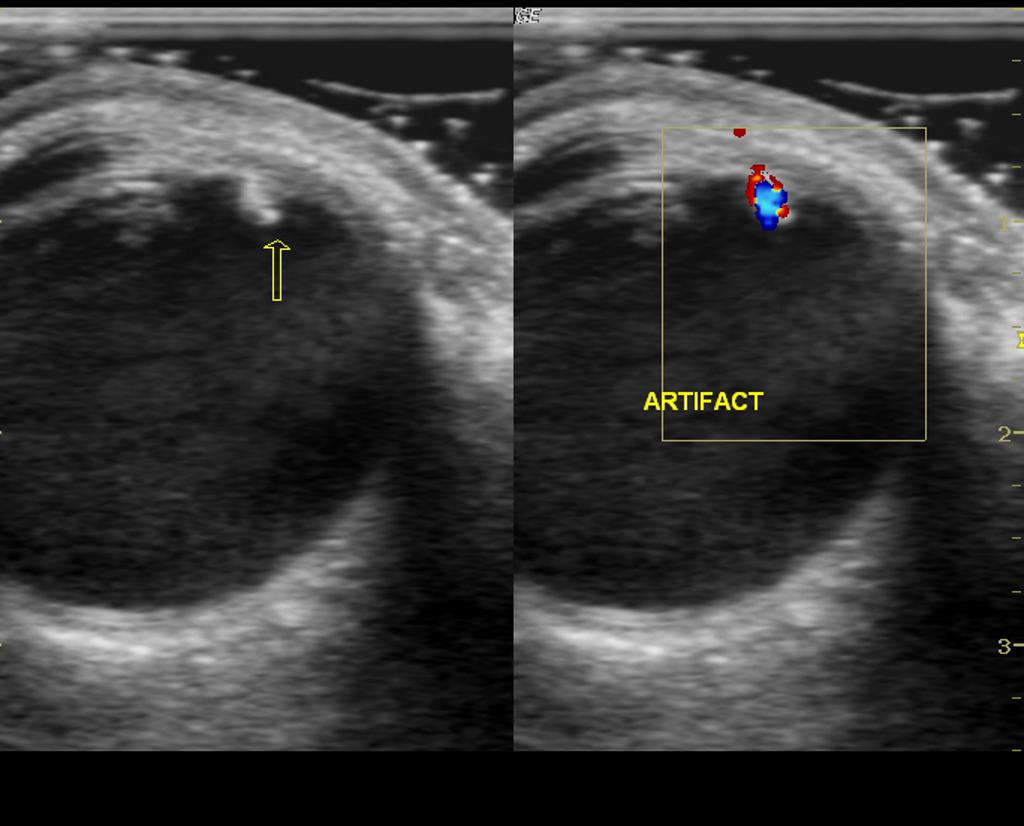

Pointofcare Ultrasound Detection of Cataract in a Patient with Vision

From westjem.com

Pointofcare Ultrasound Detection of Cataract in a Patient with Vision Eye Lens Ultrasound The most prevalent use of ocular ultrasonography is to obtain globe length in order to calculate corrective intraocular lens power requirements. 1 mechanism of ocular ultrasound. Ocular echography or ocular ultrasonography (ophthalmic ultrasound) is an important modality of ophthalmic investigation. 2 speed of sound in. Ocular ultrasound is a fast and simple technique that can be performed at the bedside. Eye Lens Ultrasound.